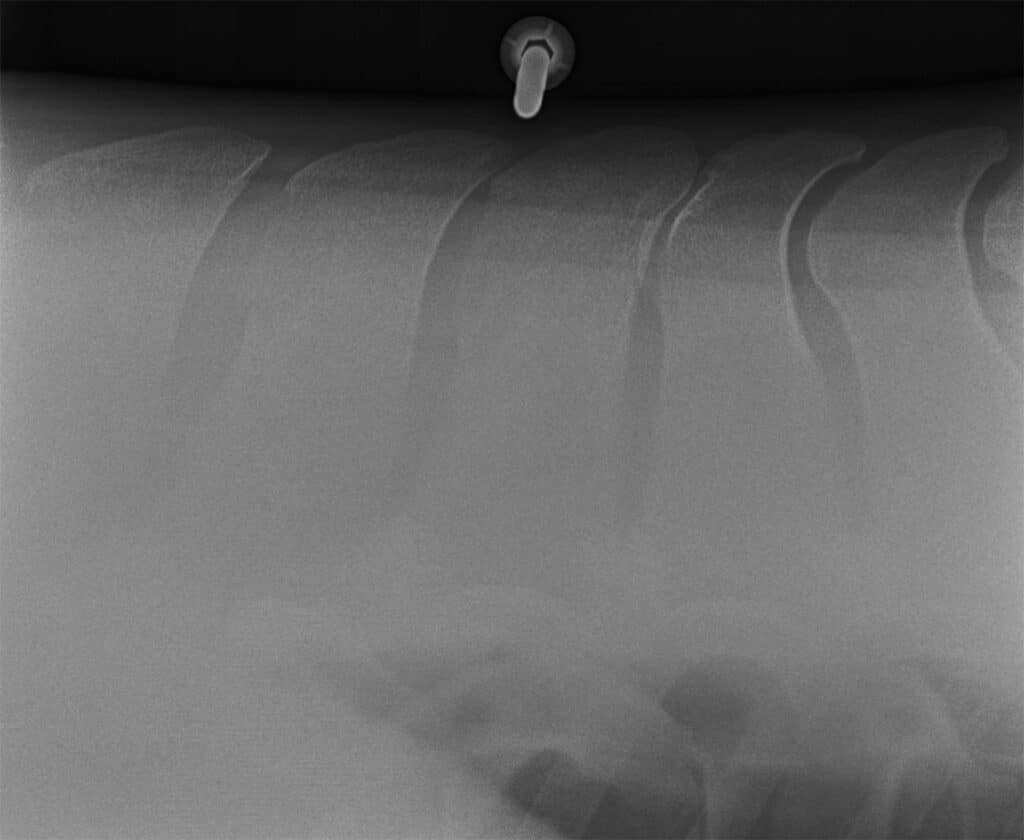

The same horse depicted in the previous X-ray, again showing kissing spines.